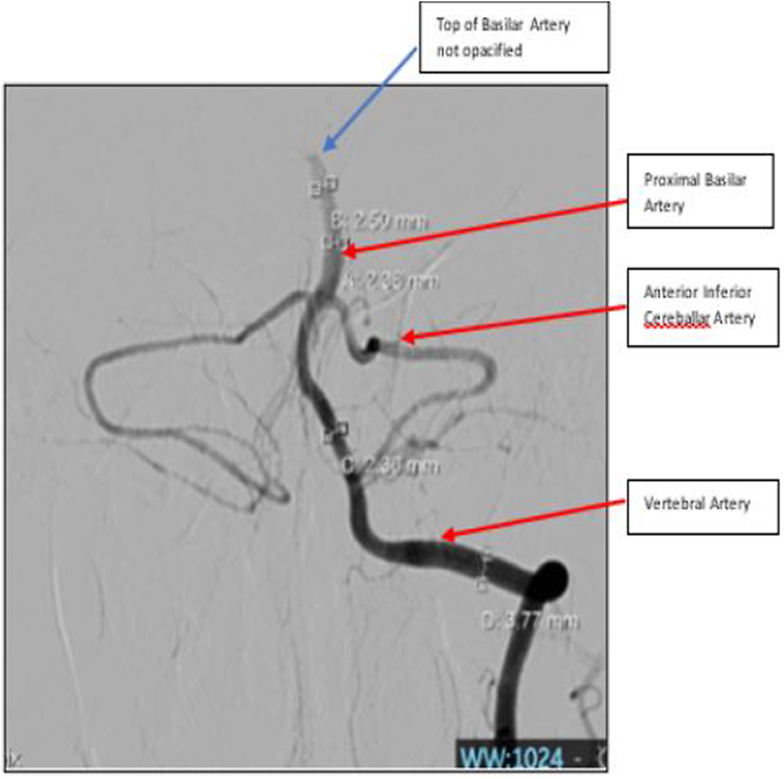

Introduction: This case report illustrates the complexities of arrhythmogenic right ventricular cardiomyopathy (ARVC) and its thromboembolic complications resulting in top-of-basilar artery syndrome. We discuss the case of a 37-year-old male with ARVC who presented with acute onset of dizziness, imbalance, and vomiting, leading to the diagnosis of a top-of-basilar artery occlusion (BAO) which was successfully treated.

Case presentation: This case highlights the diagnostic and acute treatment challenges in BAO due to its non-specific symptoms and emphasizes the critical role of CT angiography in detecting occlusive thrombi for timely intervention. With prompt endovascular thrombectomy and bridging intravenous thrombolysis, complete recanalization was achieved and the patient was discharged with modified Rankin Scale (mRS) of 1. Effective management strategies involve assessing ventricular function, detecting arrhythmias, identifying intracardiac thrombi, and implementing individualized stroke prevention measures, such as using direct oral anticoagulants.